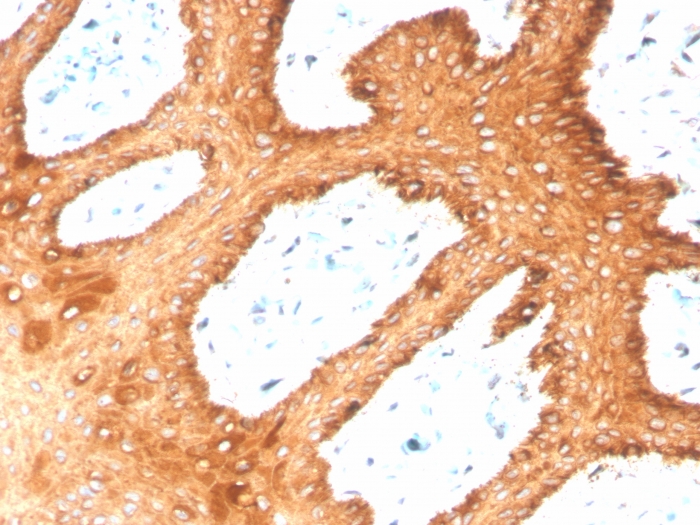

IHC-P analysis of human skin tissue section using GTX02665 Cytokeratin 2 antibody [KRTH/4392R].

IHC-P analysis of human skin tissue section using GTX02665 Cytokeratin 2 antibody [KRTH/4392R].